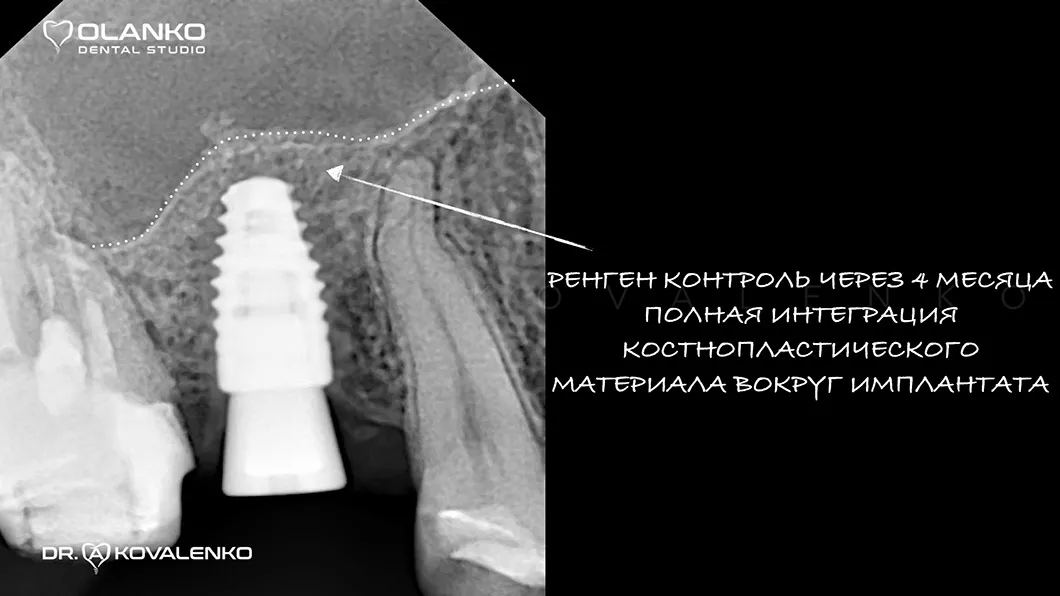

Костная пластика – это хирургическая операция, которая позволяет восстановить объём челюстной кости, для будущей зубной имплантации, с помощью костной ткани, взятой в донорских зонах у пациента, или искусственного костнопластического материала, а также смеси костных материалов.

Операция костной пластики может выполнятся как самостоятельно, так и совместно с установкой зубного имплантата.

В Olanko dental studio (Оланко) г. Бровары мы выполняем весь спектр операций костной пластики на верхней и нижней челюсти, а так же наращиваем костную ткань в области гайморовой пазухи (верхнечелюстного синуса).